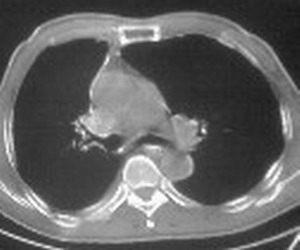

先考虑:右下肺中心型肺癌伴下叶肺不张、胸腔积液

右肺下叶支气管闭塞,中间段支气管狭窄,下叶不张,胸腔及叶间积液.中心型肺癌伴下叶肺不张.胸腔和叶间积液.

考虑:右下肺中心型肺癌伴下叶肺不张、胸腔积液

右肺下野后部均匀低密度影,边缘锐利,前缘外突(不支持肺不张),纵隔内未见明显肿大淋巴结,右下肺门结构显示欠清,临床资料太过简单,考虑右侧后胸部包裹性积液。其他待排。建议密切结合临床其他检查。

考虑右下肺中心型肺癌伴下叶肺不张、胸腔积液。